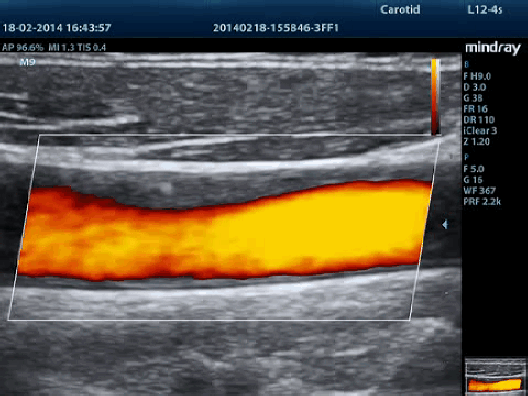

Auto IMT (автоматическое определение толщины комплекса интима-медиа)

Автоматическое измерение толщины передней и задней стенки, предоставляющее точную информацию о состоянии сонной артерии.